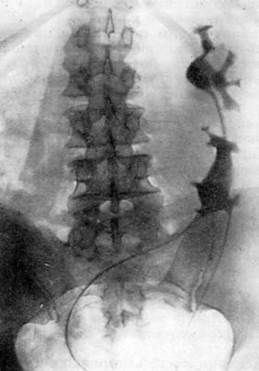

Экскреторная урография при нефроптозе: диагностические изображения